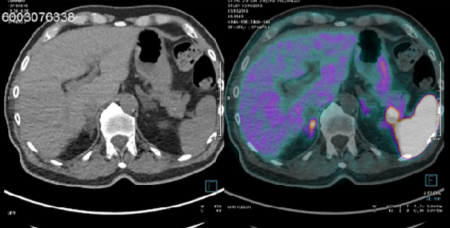

Intrapancreatic accessory spleen false positive to 68Ga-Dotatoc: case report and literature review | World Journal of Surgical Oncology | Full Text